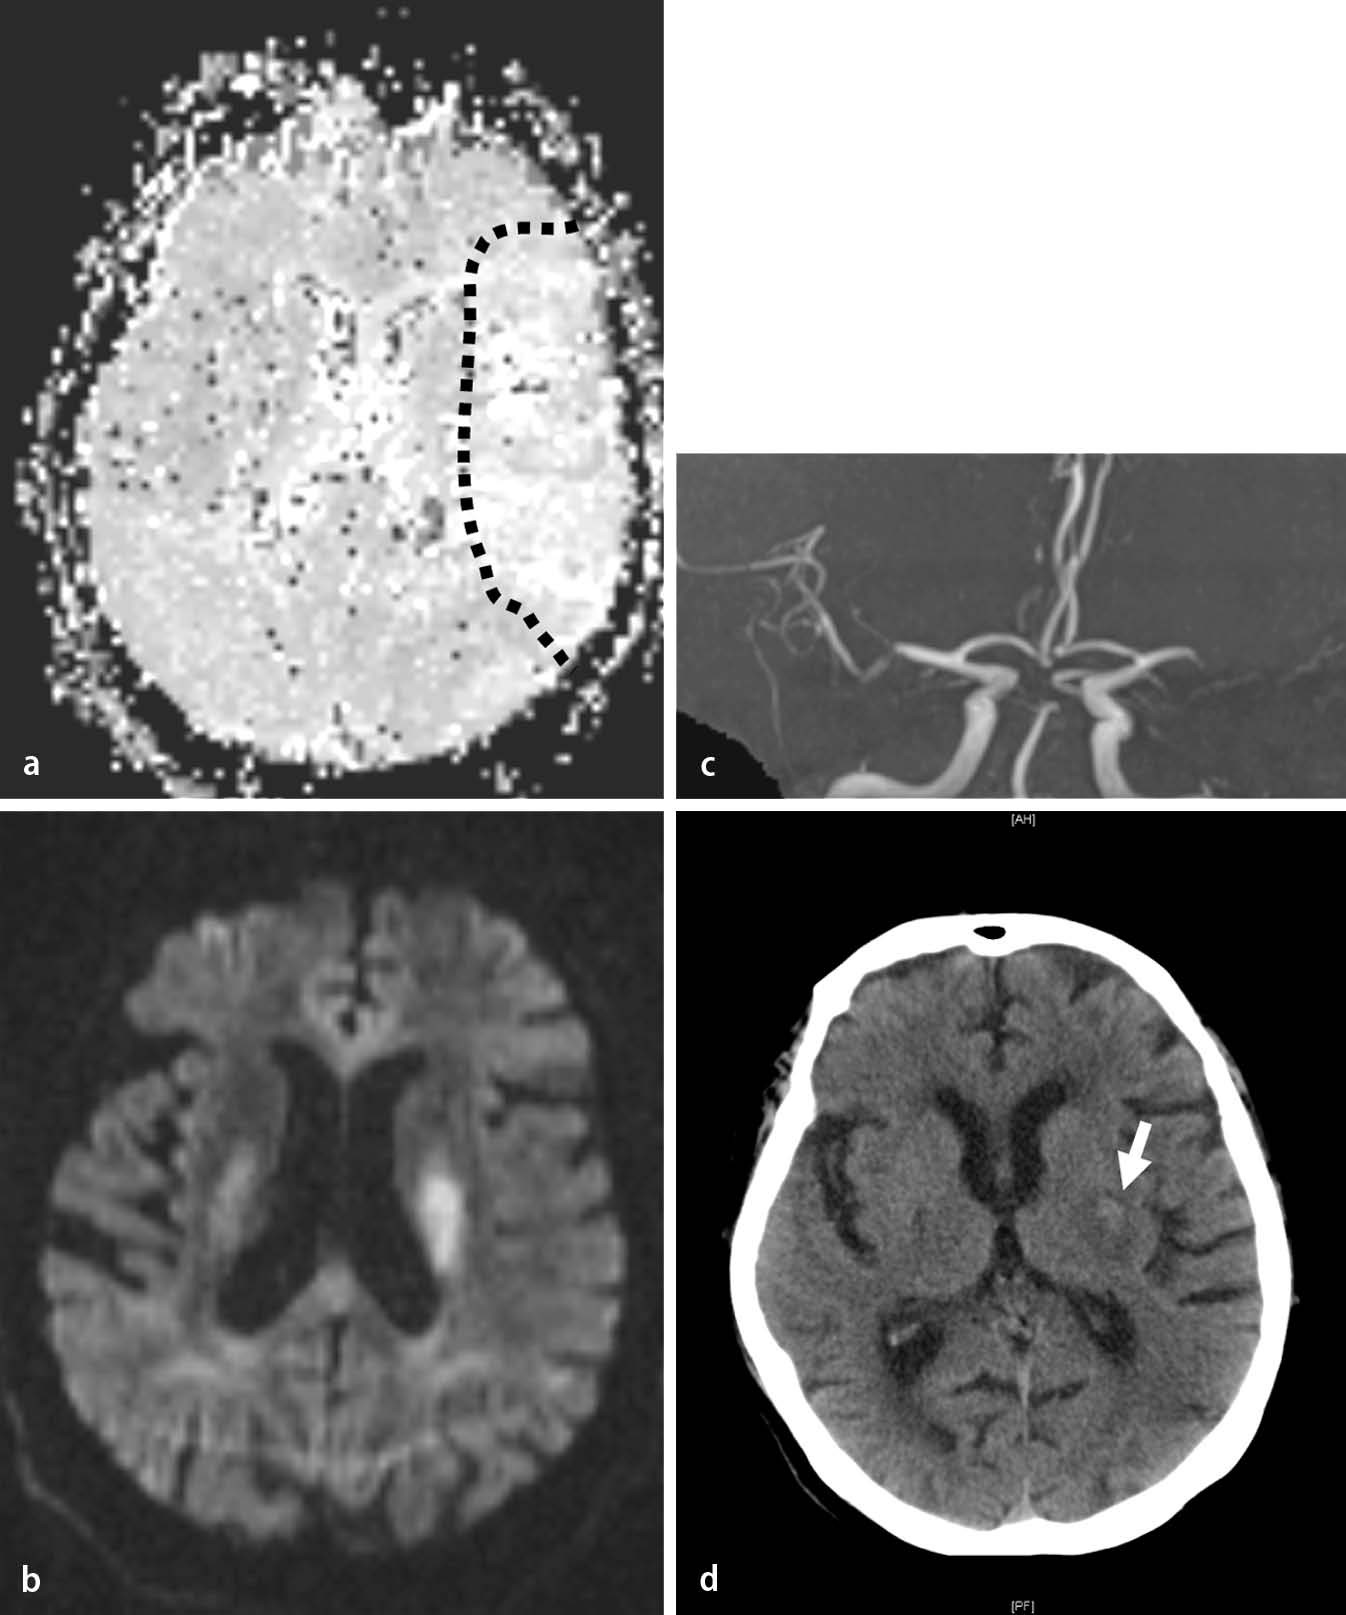

Patientenzentrierung Statt Zeitfenster

Diagnostik Mit Hindernissen Stroke Mimics Und Kindlicher Schlaganfall

Akuter Ischamischer Schlaganfall Moderne Techniken Verkurzen Die

Wake Up Stroke Lyse Hilft Oft Noch Springerlink